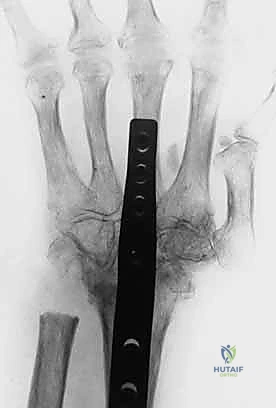

2. التدخل الجراحي المتقدم (خبرة الأستاذ الدكتور محمد هطيف)

عندما يفشل العلاج التحفظي، أو إذا كان التشوه ثابتاً ومتيبساً، أو في حالات الروماتويد المتقدمة، يصبح التدخل الجراحي حتمياً لاستعادة وظيفة اليد. يُعد الدكتور هطيف رائد عمليات جراحة اليد الميكروسكوبية في اليمن، ويستخدم تقنيات حديثة تضمن أعلى نسب النجاح.

أ) جراحات تشوه العروة (Boutonnière Surgery):

- إصلاح الوتر المباشر: خياطة الشريط المركزي الممزق إذا كانت الإصابة حديثة.

- إعادة بناء الوتر (Tendon Reconstruction): باستخدام رقعة وترية (Graft) في الحالات القديمة.

- تحرير الأنسجة (Tenolysis): فك الالتصاقات التي تمنع حركة الوتر بحرية.

خطوات العملية الجراحية: رحلة المريض داخل غرفة العمليات

يحرص الأستاذ الدكتور محمد هطيف على اتباع أقصى معايير الأمان والتعقيم العالمية في جميع عملياته. إليك نظرة تفصيلية على مجريات الجراحة:

- التخدير: غالباً ما يتم إجراء هذه العمليات تحت التخدير الموضعي أو الناحي (تخدير الذراع فقط)، مما يسمح للمريض بالتواصل مع الجراح أثناء العملية للتأكد من نجاح حركة الأوتار.

- الشق الجراحي الميكروسكوبي: يتم عمل شق دقيق جداً فوق المفصل المتضرر لتجنب الإضرار بالأعصاب والأوعية الدموية الدقيقة.

- الإصلاح الديناميكي:

- في تشوه العروة، يتم خياطة الشريط المركزي وإعادة وضع الأشرطة الجانبية في مكانها الصحيح أعلى المفصل.

- في تشوه عنق البجعة، يتم شد الصفيحة الراحية أو إجراء نقل دقيق للأوتار.

- الاختبار الحركي: يطلب الدكتور هطيف من المريض (إذا كان التخدير موضعياً) تحريك إصبعه لضمان التوازن المثالي قبل إغلاق الجرح.

- الإغلاق والتثبيت: يُغلق الجرح بخيوط تجميلية دقيقة، ويتم وضع الإصبع في جبيرة مخصصة لحماية الإصلاح الجراحي.